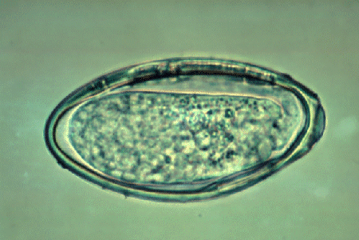

Bij sommige paarden zijn wormen zichtbaar in de mest, maar vaak blijft een besmetting onopgemerkt met het blote oog. De aanwezigheid van wormeieren kan enkel worden vastgesteld via een gespecialiseerd mestonderzoek. Aangezien er verschillende soorten wormen bestaan, is een gerichte aanpak per type noodzakelijk voor een doeltreffende behandeling.

Het mestonderzoek wordt in eigen praktijk uitgevoerd, waardoor we snel een resultaat kunnen garanderen. U kunt mest van uw paard per post (goed verpakt) opsturen of persoonlijk afgeven in de praktijk voor analyse.

Mestonderzoek

Consult aan huis